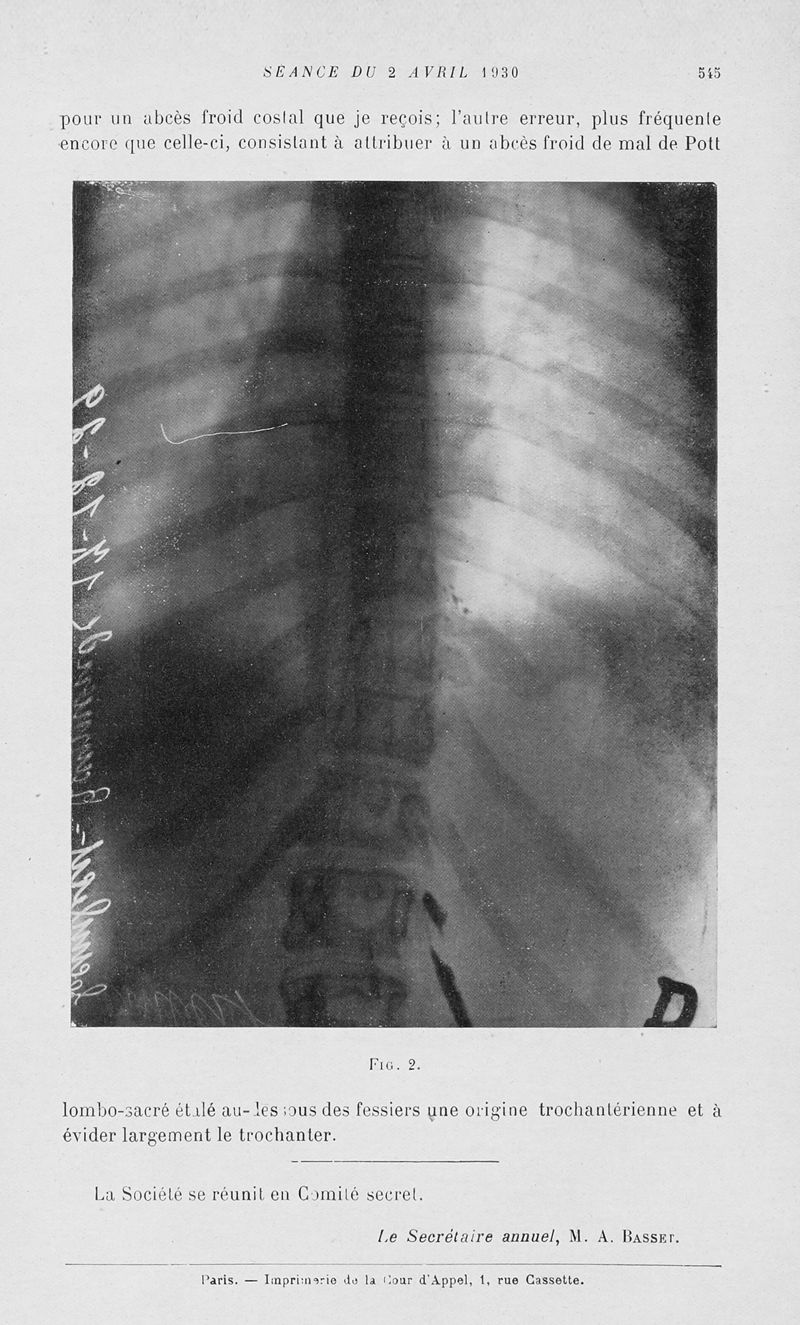

Bulletins et mémoires de la société nationale de chirurgie

Tome LVI, 1930. - Paris : Masson, 1930.